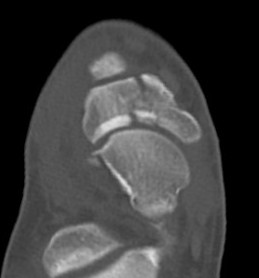

CT

Minimally displaced navicular stress fracture

Displaced navicular stress fracture